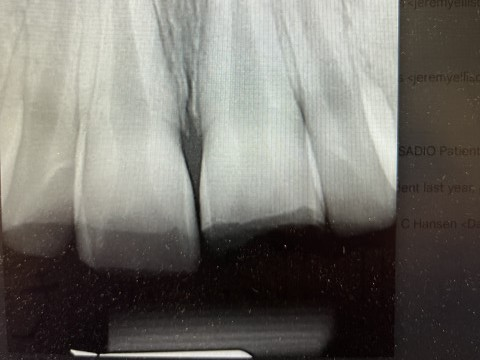

DentXpinTM – placed April, 12, 2012 and still holding strong.

1